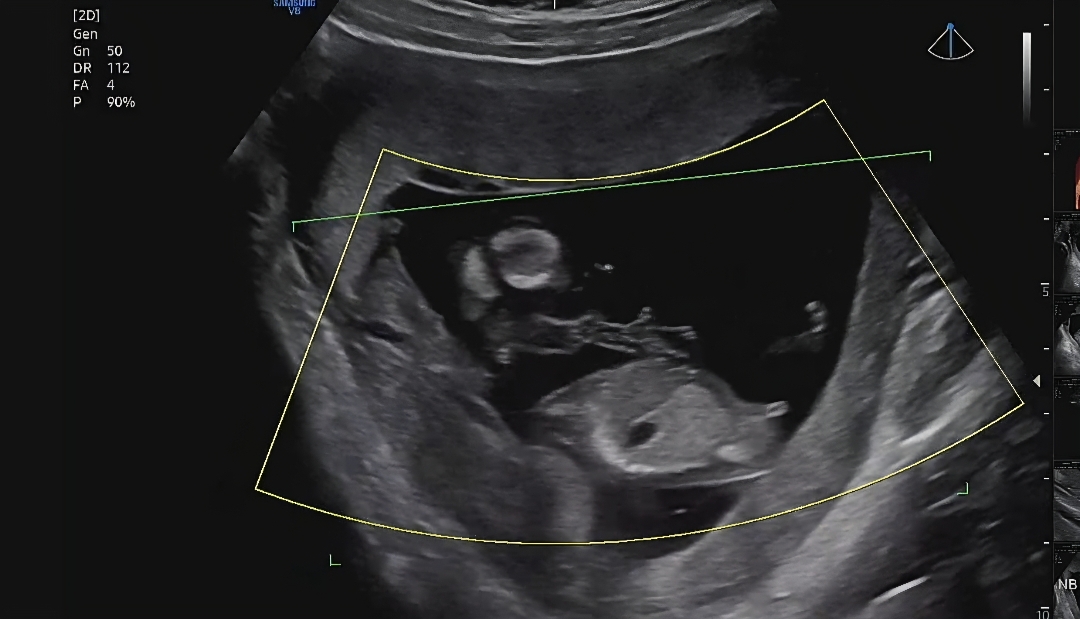

각도법 한번 봐주세요!

12주차 기형아검사 하고왔어요! 이 사진으로올리는게 맞나 싶지만 조금 궁금해서요ㅎㅎ아들 딸 중에 어떤거 같으신가요?